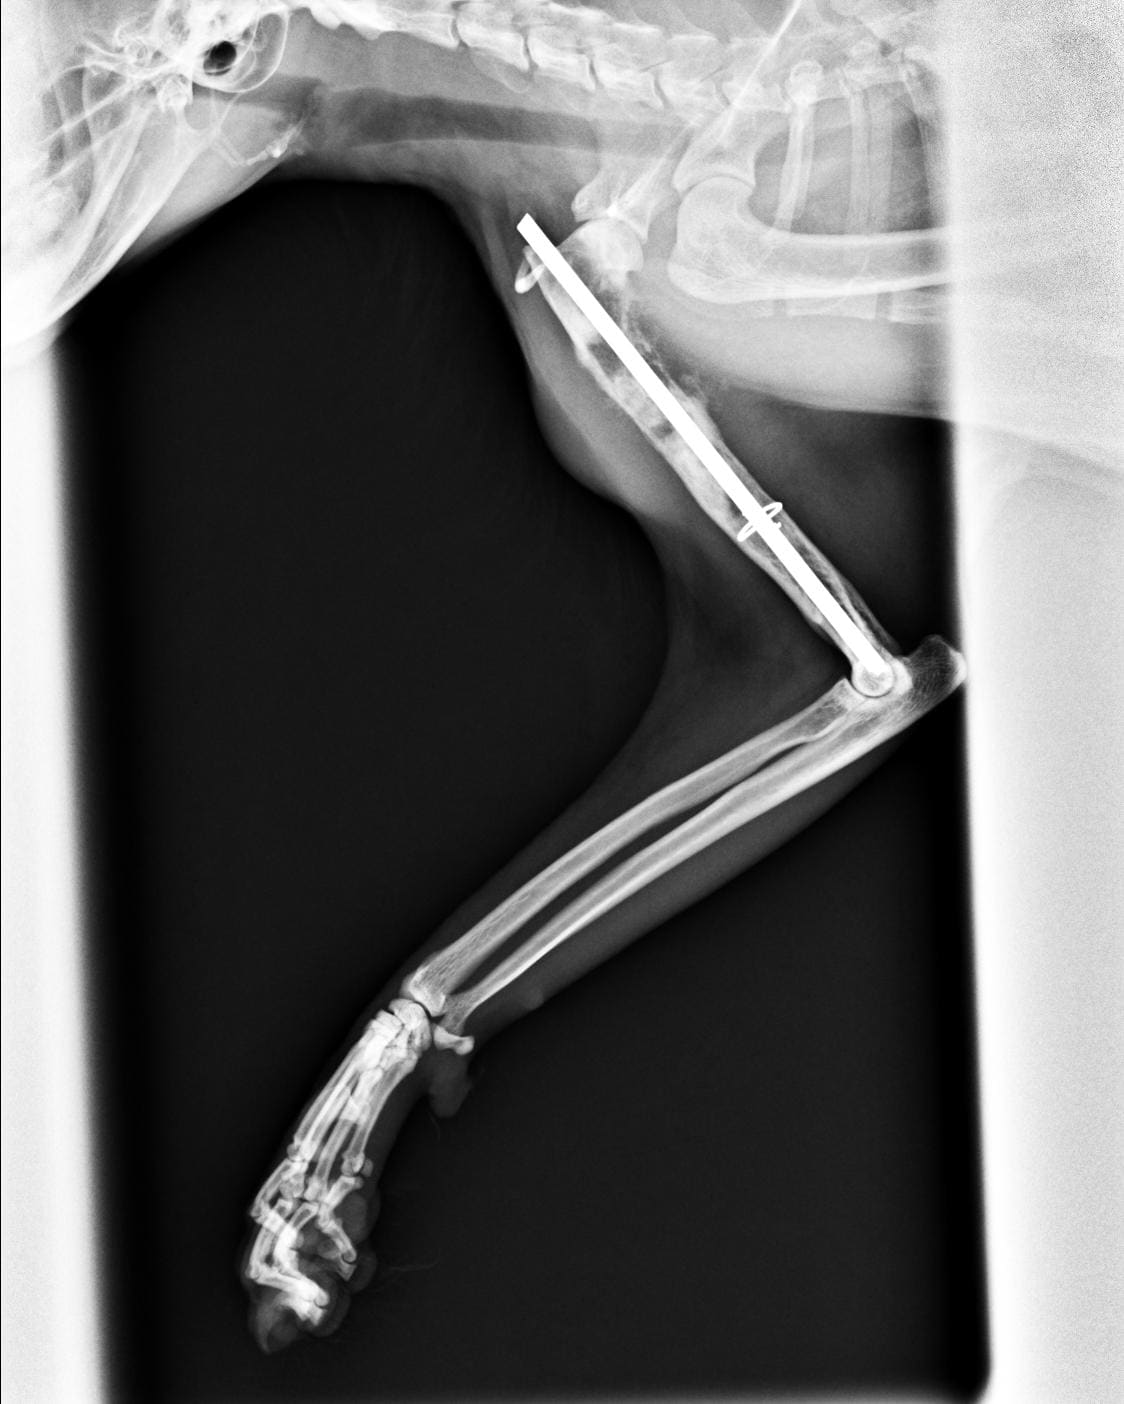

hi I live in Iran.I have a cat of 4 to 5 years old. before I got her she had been operated on and they planted a pin in her hand. I was told that the pin should not be removed but now her hand hurts. I was told by a vet that she has bone infection , another one said that the bone is breaking down and another one said that the pin should be removed. there are radiology images one from a month ago and one from yesterday. can you tell me what is wrong with her? thanks for your help.

Hello and thank you for your post! It does look like there is weakening and loss of bone around the pin. I would definitely have this pin removed and then place Pashi in a splint for several weeks until the bone recovers. The first thing I noticed with this is that the pin is quite large in diameter and may be taking up too much space which could have led to this happening. I would schedule a recheck with your vet to possibly have it removed. Please do not hesitate to contact me with any further questions or concerns.